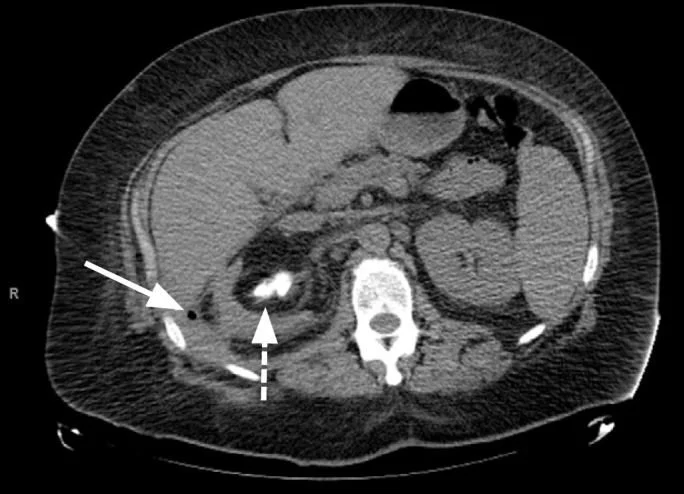

A 63 y.o. female presents with R flank pain

What do you see on CT?

The condition can be recognized on CT where it often is associated with a staghorn calculus as in the case of our patient or the “bear paw sign”.

Above is a R perinephric hematoma in a patient with a ruptured renal cyst on eliquis. He required transfusions and had had a previous perinephric bleed on the L.